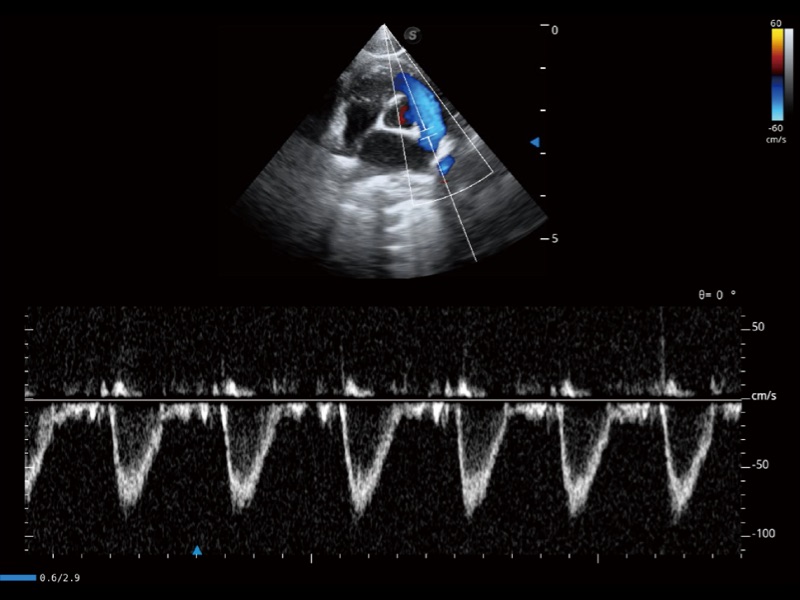

通过360度任意调节3条M型取样线,在同一心动周期上观察心脏不同位置的运动曲线,得到准确的心功能测量数据,有效评估心肌运动及左心室功能。